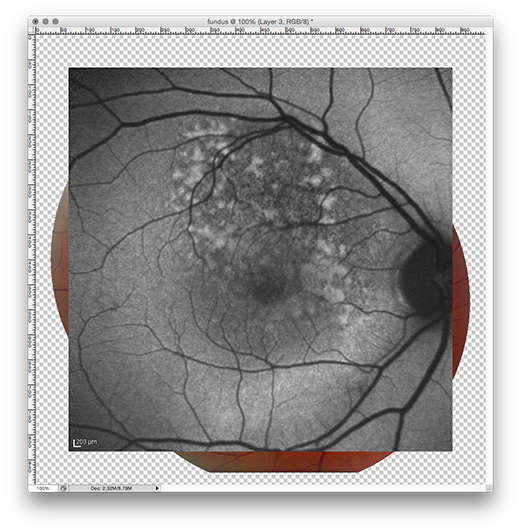

In the recently created collage window (now titled fundus.jpg) of Photoshop:

• This will add the previously copied FA image as a third layer to the collage.

PasteFA

• Change the opacity of layer 3 to 50%.

• Transform the FA layer by rotating and rescaling using the blood vessels and disc as landmarks.

• To finalize the transform click the check mark in the toolbar.

RescaleFA